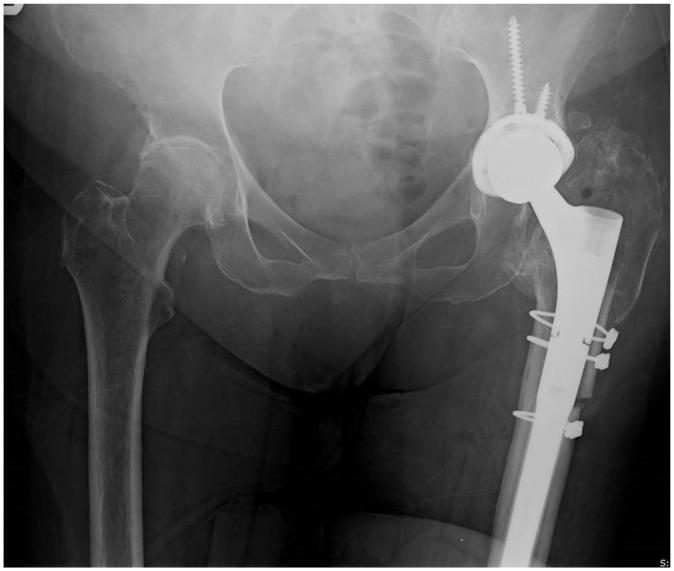

大转子延长截骨术:改善翻修全髋关节置换术的手术入路并降低风险

Extended trochanteric osteotomy: improving the access and reducing the risk in revision THA.

This review article presents a comprehensive literature review regarding extended trochanteric osteotomy (ETO).The history, rationale, biomechanical considerations as well as indications are discussed.The outcomes and complications as reported in the literature are presented, discussed and compared with our own practice.Based on the available evidence, we present our preferred technique for performing ETO, its fixation, as well as post-operative rehabilitation.The ETO aids implant removal and enhanced access. Reported union rate of ETO is high. The complications related to ETO are much less frequent than in cases when accidental intra-operative femoral fracture occurred that required fixation.Based on the literature and our own experience we recommend ETO as a useful adjunct in the arsenal of the revision hip specialist. Cite this article: 2020;5:104-112. DOI: 10.1302/2058-5241.5.190005.

摘要

这篇综述文章对大转子延长截骨术(ETO)进行了全面的文献综述。讨论了其历史、原理、生物力学考量以及适应症。呈现并讨论了文献中报道的结果和并发症,并与我们自己的实践进行了比较。基于现有证据,我们介绍了进行ETO的首选技术、其固定方法以及术后康复。ETO有助于取出植入物并增加手术入路。报道的ETO愈合率很高。与ETO相关的并发症比术中意外发生股骨骨折需要固定的情况要少得多。基于文献和我们自己的经验,我们推荐ETO作为髋关节翻修专家的有用辅助手段。引用本文:2020;5:104 - 112。DOI:10.1302/2058 - 5241.5.190005。